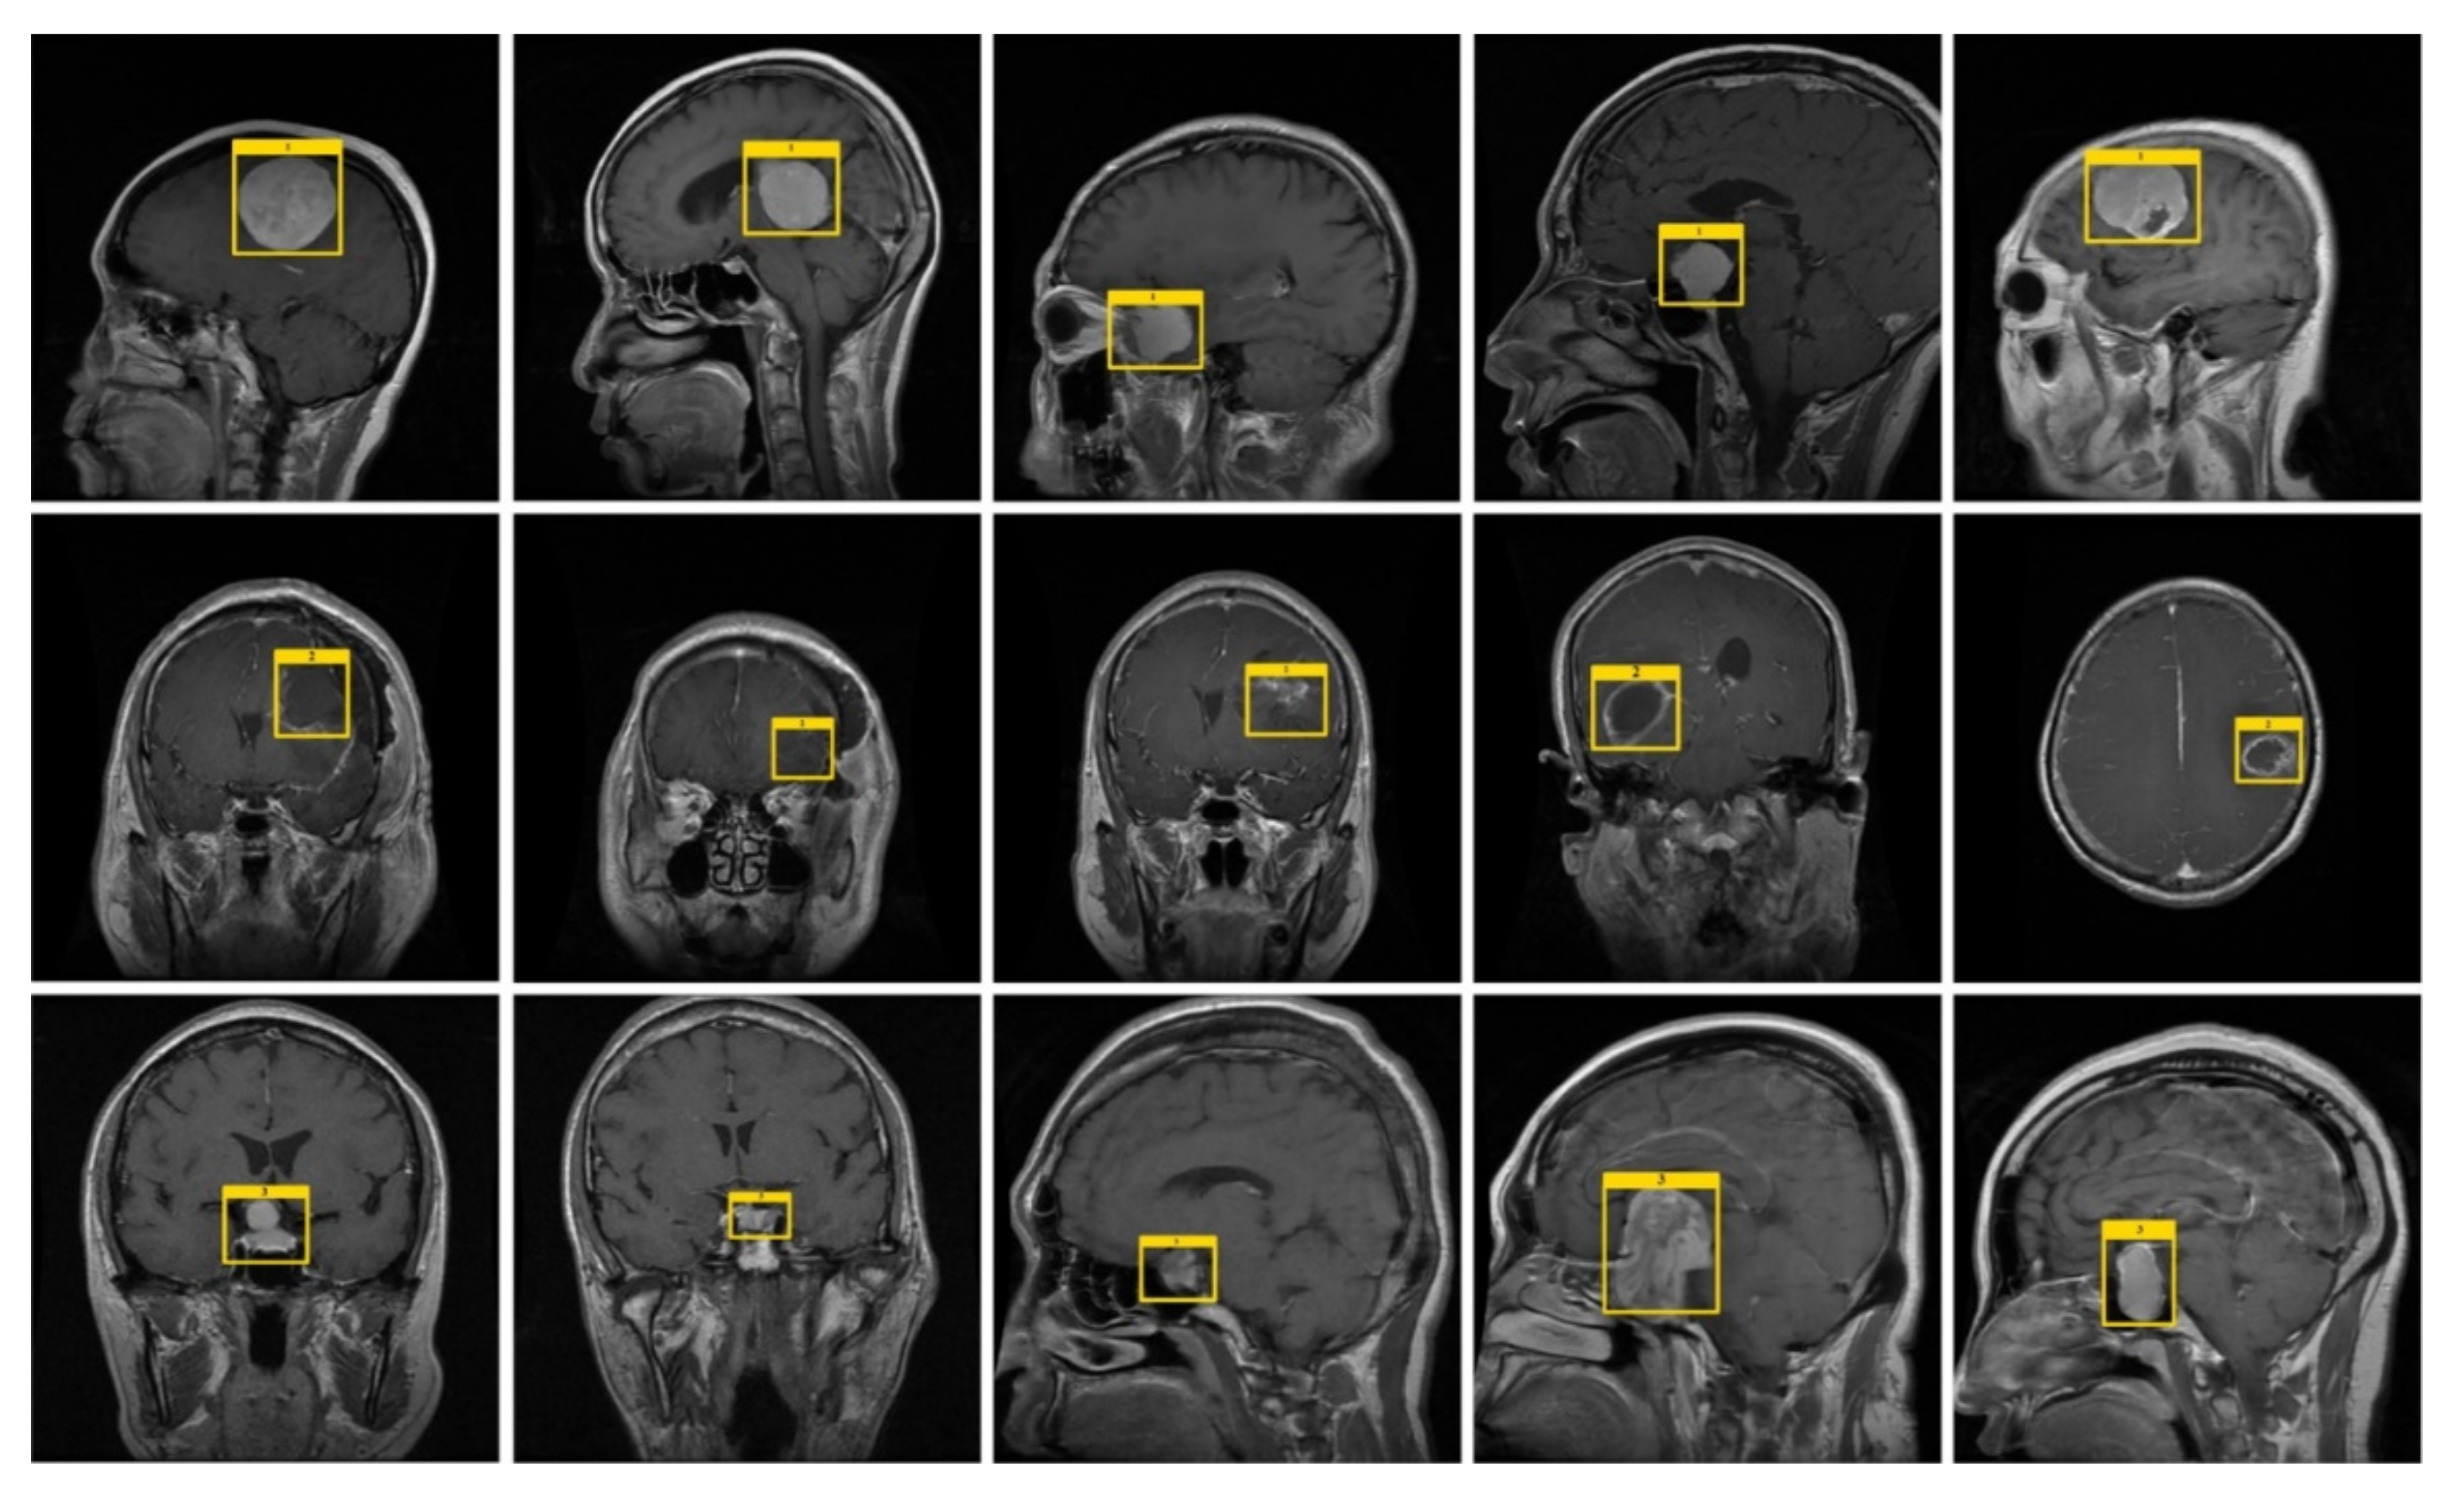

3.1. Annotations

4.1. Dataset